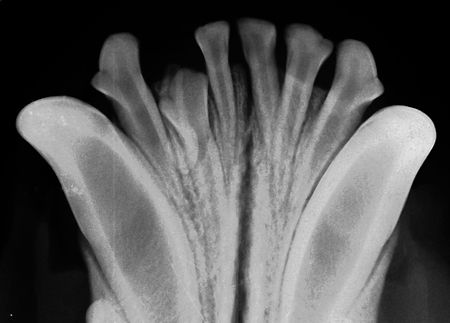

Rockville, Md. -- The U.S. Food and Drug Administration issued a safety warning to veterinarians about the use (and purchase) of some hand-held dental X-ray units sold over the Internet from foreign sources.